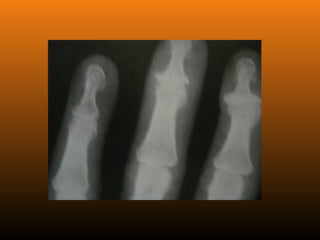

EROSIVA:Também conhecida como osteoartrose inflamatória.

reumatóide negativo)

RADIOLOGIA

No início da doença não se observam anormalidades. Com seu

desenvolvimento, observam-se:

 Diminuição do espaço intra-articular

 Esclerose subcondral (eburnação)

 Osteófitos;

 Erosão e anquilose óssea (pseudocistos ósseos).

PRIMÁRIA (idiopática): Ocorrena ausência de qualquer fator predisponente conhecido e se subdivide em duas categorias, localizada e generalizada (inclui 3 ou mais áreas). SECUNDÁRIA: É aquela em que se reconhece uma causa ou um fator preexistente. EROSIVA:Também conhecida como osteoartrose inflamatória. Acomete as articulações IFD e IFP nas mãos, com FR (fator reumatóide negativo) ClassificaçãoClassificação